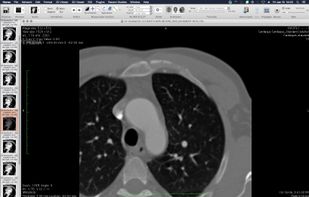

Weasis is a multipurpose standalone and web-based DICOM viewer with a highly modular architecture. It is a very popular clinical viewer used in healthcare by hospitals, health networks, multicenter research trials, and patients.

Weasis is a multipurpose standalone and web-based DICOM viewer with a highly modular architecture. It is a very popular clinical viewer used in healthcare by hospitals, health networks, multicenter research trials, and patients.